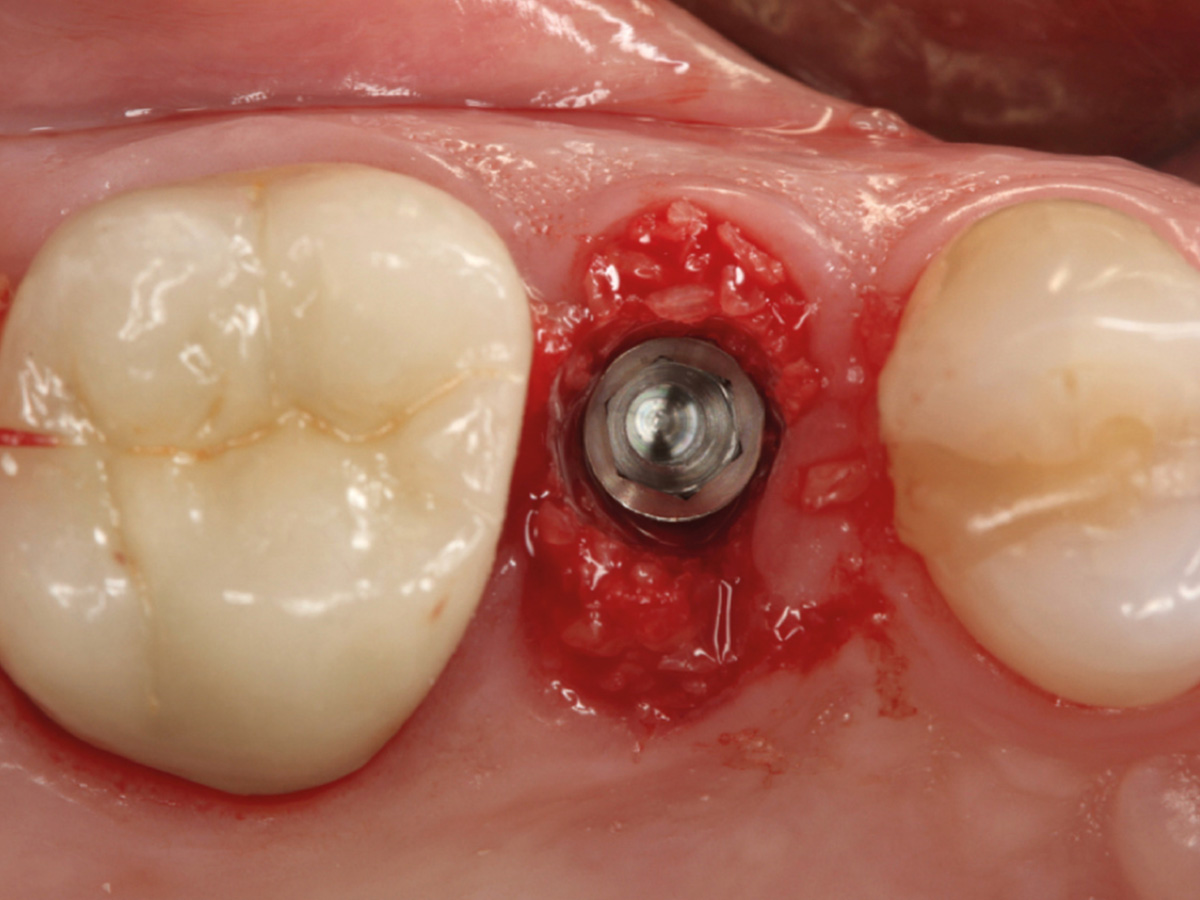

• Implantatbettoptimierung mit Densah®-Bohrer zur Erhöhung der Primärstabilität (z.B. bei Sofortimplantation/-versorgung)